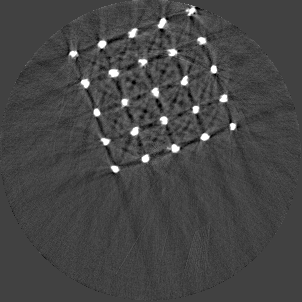

Figure 5 illustrates a single slice spectral reconstruction of the Ti scaffold. Varying levels of streak artefacts can be seen across the spectral reconstructions. The spectral reconstructions for the energy ranges 35 to 80 keV, 55 to 80 keV, and 62 to 80 keV shown in figure 5, exhibit reduced streak artefacts. A region-of-interest (ROI) analysis was performed in the immediate vicinity of the metal region where the streaks are more pronounced. Average attenuation coefficent of air close to zero conveys less regional noise/artefacts. The regional average attenuation coefficient () of the non-metal (air) region in 55 to 80 keV reconstruction (figure 5c) shows reduced artefacts. Even though minor streaks and statistical noise appear in figure 5d due to photon limitation, the artefacts are less pronounced in comparison to the wide energy acquisition in figure 5a.